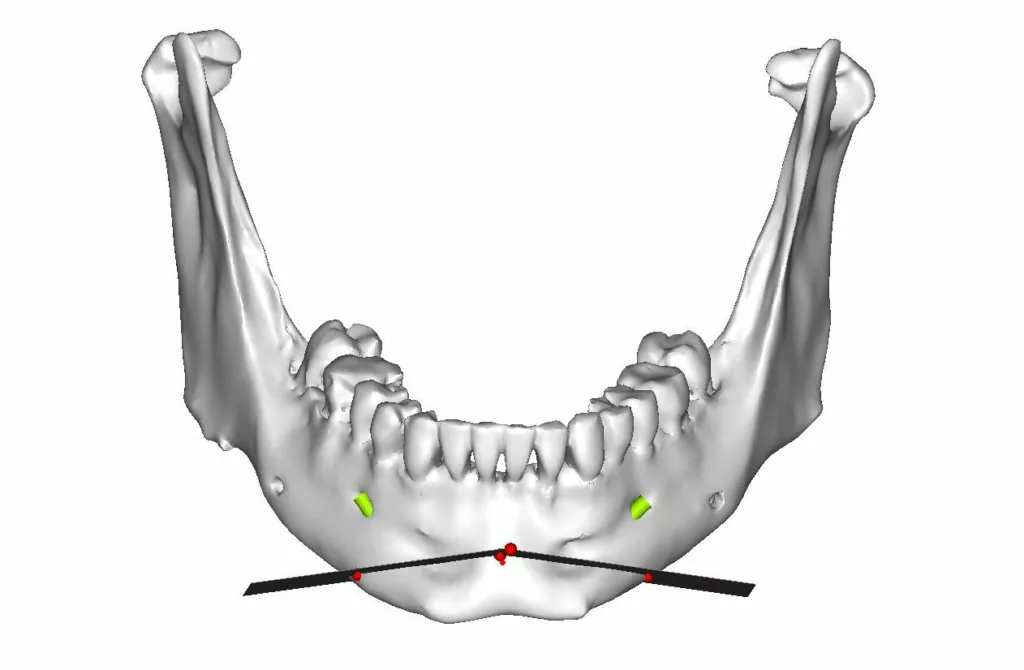

La chirurgie guidée consiste à simuler le geste opératoire au moyen de logiciels spécialisés puis à assurer le contrôle de l’exécution chirurgicale au bloc opératoire à l’aide de guides de découpe osseuse et de forage.

Des miniplaques en titane sur mesure spécifiques de l’anatomie propre à chaque patient et spécifiques des mouvements envisagés par le chirurgien permettent de stabiliser toutes les pièces anatomiques libérées par les manœuvres d’ostéotomie conformément à la simulation : plateau maxillaire, arc denté mandibulaire, branches montantes et condyles, menton .

Ostéotomie de Lefort I en 1, 2 ou 3 fragments, ostéotomie sagittale des branches montantes, génioplasties, ostéotomies segmentaires maxillaires et mandibulaires, postérieures ou antérieures, plus rarement ostéotomies de Lefort II ou Lefort III, tous les types d’ostéotomies peuvent être réalisés en chirurgie guidée.